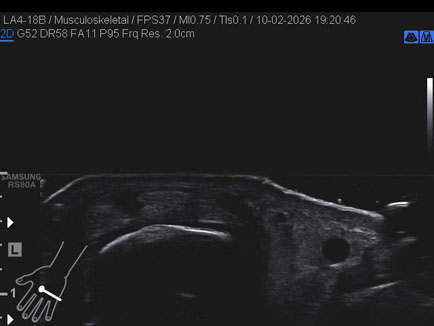

Data inserimento: 13/02/2026

Ecografia del: 10/02/2026

Strumento: Samsung

Sonda: Lineare

Commento all'esame: rottura della bandelletta laterale MTC-F del II° dito con conseguente lussazione del tendine estensore.

Conclusioni: rottura della bandelletta laterale metacarpo-falangea del 2° dito della mano sinistra (tear of the lateral band of the metacarpophalangeal - MCP - joint of the left index finger).

Realizzazione: Dr. F. Pietro Tarini - Gubbio (PG)